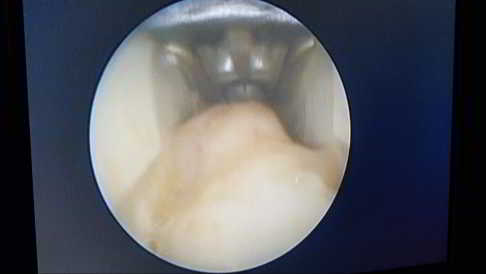

Über den endoskopischen Zugang wird das Morton Neurom ausschließlich nervenerhaltend operiert, nicht nervenentfernend.

Bei der endoskopisch durchgeführten Osteotomie kann diese Operation unter direkter endoskopischer Sicht auf die beteiligten Metatarsalknochen erfolgen. Bei der offenen Operation wird die Osteotomie des Metatarsalknochens über den Röntgenbildwandler verfolgt.